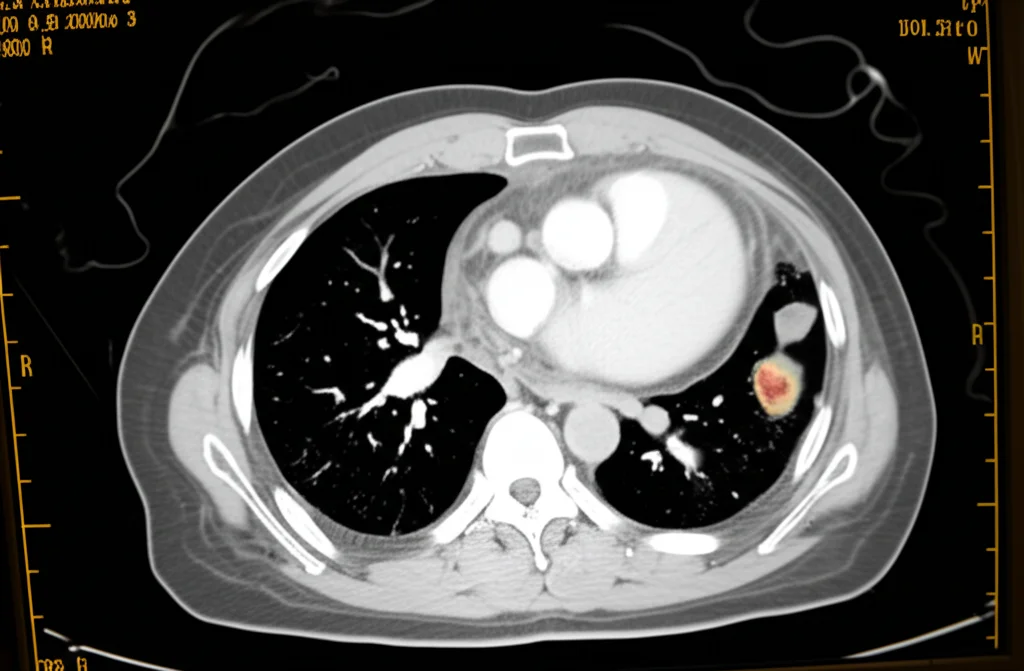

Cosa significa questo? Significa che la valutazione multidisciplinare permette una stadiazione pre-operatoria più accurata. Probabilmente, come suggeriscono gli autori, grazie a una revisione più attenta delle immagini da parte di radiologi dedicati e all’implementazione della stadiazione mediastinica pre-operatoria (con tecniche come l’ecografia endobronchiale – EBUS) da parte degli pneumologi interventisti. Questo evita di portare in sala operatoria pazienti che potrebbero beneficiare maggiormente di trattamenti neoadiuvanti (cioè fatti prima dell’intervento).

E qui arriva un’altra bella notizia. Nei pazienti operati con intento curativo, l’introduzione dell’MDT ha portato a un aumento significativo delle diagnosi in stadio precoce (p=0.003). Addirittura, tra i pazienti in stadio I (il più iniziale), si è visto un netto incremento dei tumori piccolissimi (pT1a, dal 2,5% al 15,1%) e una contemporanea riduzione di quelli leggermente più grandi (pT2a, dal 46,2% al 23,8%). Questo suggerisce che la revisione collegiale delle immagini permette di cogliere cambiamenti minimi nei noduli polmonari, portando a diagnosi più tempestive. Inoltre, nel gruppo MDT si è osservato un tasso significativamente più alto di resezioni anatomiche (lobectomie e segmentectomie, considerate più radicali dal punto di vista oncologico) rispetto alle resezioni atipiche (wedge resection).